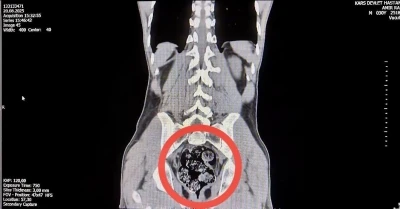

Asayiş 5 gün önce İşçinin makatına ’şaka’ olsun diye hava bastı, kalın bağırsağı patladı: 1 tutuklama Asayiş 1 hafta önce Makatına hava basılması sonucu ölen çocuğun olayına ilişkin 3 hastane personeli açığa alındı Asayiş 1 hafta önce Makatına hava basılması sonucu ölen çocuğun olayına ilişkin 3 hastane personeli açığa alındı Gündem 2 hafta önce Kompresörle eziyet edilen çocuk ölmüştü: 3 hastane çalışanı açığa alındı! Asayiş 2 hafta önce Makatına hava basılması sonucu ölen çocuğun faili ile çalıştığı atölyede halay çektiği görüntüleri ortaya çıktı Gündem 2 hafta önce Şanlıurfa'da kompresörle işkenceden ölen çocuğun ailesi sessizliğini bozdu Asayiş 2 hafta önce Makatına hava basıldığı için ölen çocuk defnedildi Asayiş 2 hafta önce Sözde şaka ölümle bitti: Makatından kompresörle hava basılan çocuk kurtarılamadı Asayiş 2 hafta önce Sözde şaka ölümle bitti: Makatından kompresörle hava basılan çocuk kurtarılamadı Gündem 3 hafta önce Çocuk işçiye kompresörle akılalmaz işkence! Asayiş 3 ay önce Kars’ta İranlı kuryenin makatından uyuşturucu çıktı